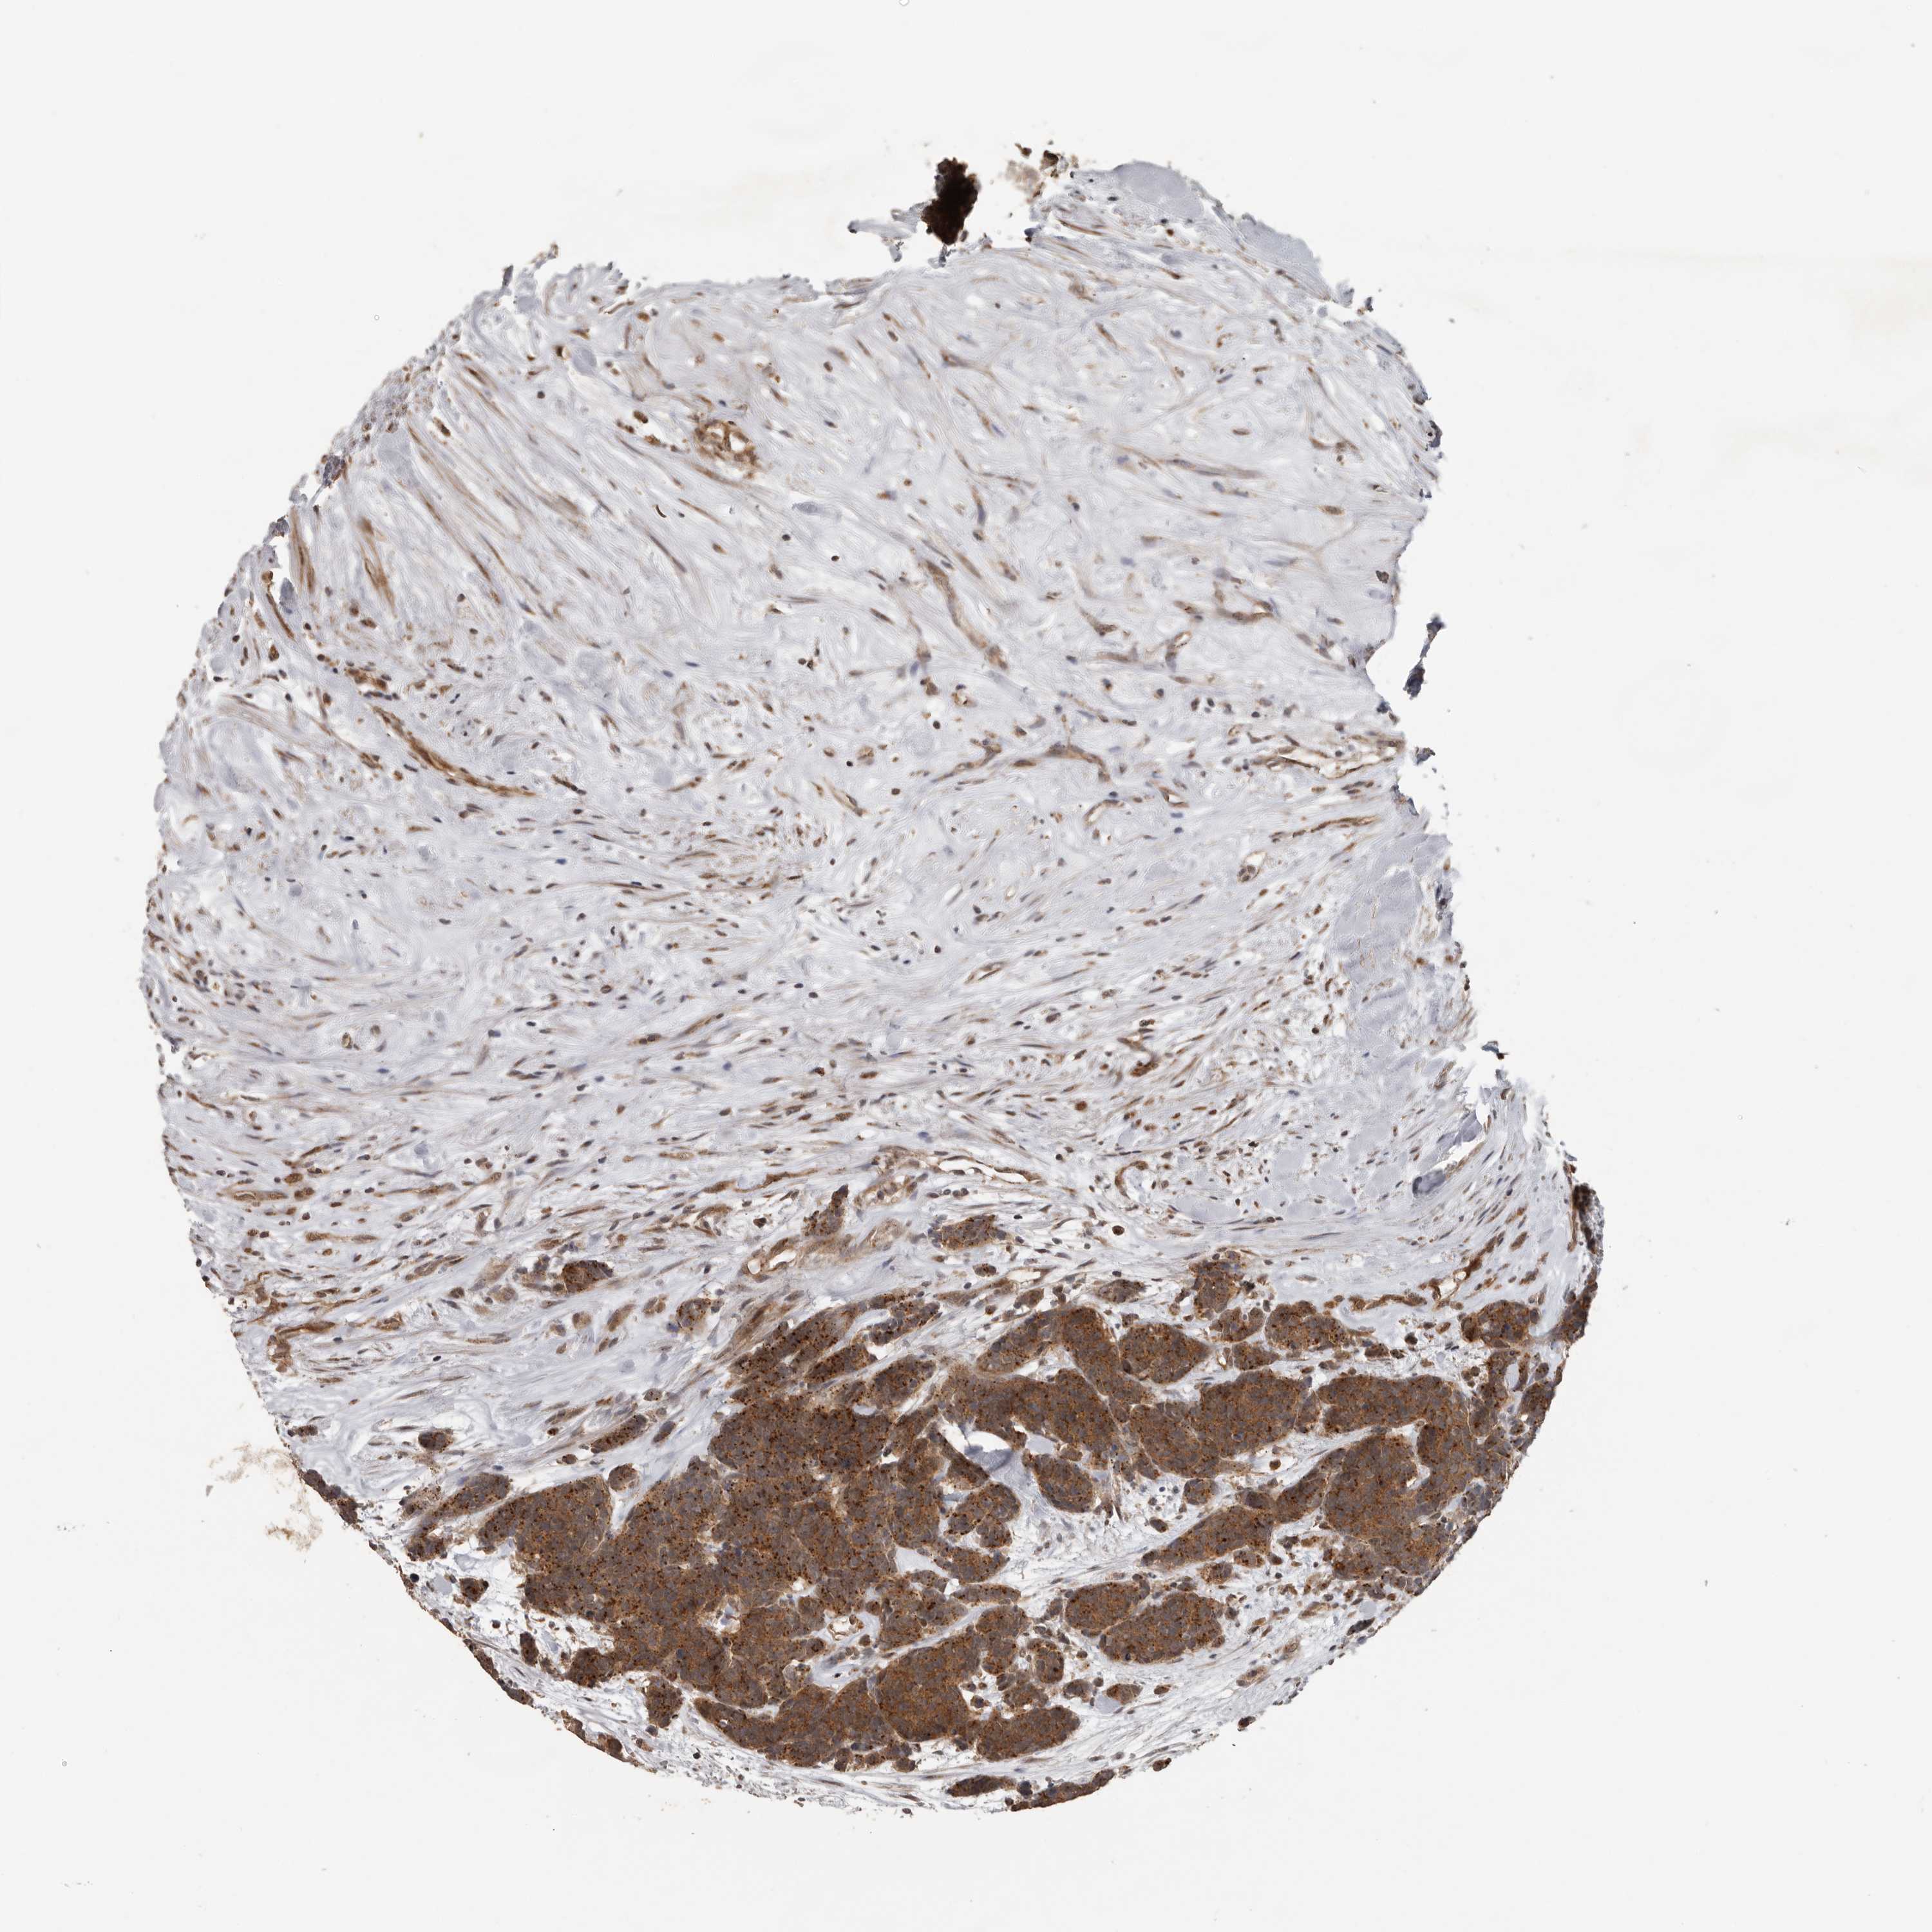

CARCINOID - Protein expressioni

A mouse-over function shows sample information and annotation data. Click on an image to view it in a full screen mode. Samples can be filtered based on level of antibody staining by selecting one or several of the following categories: high, medium, low and not detected. The assay and annotation is described here.

Antibody stainingi

Antibody staining in the annotated cell types in the current human tissue is reported as not detected, low, medium, or high, based on conventional immunohistochemistry profiling in selected tissues. This score is based on the combination of the staining intensity and fraction of stained cells.

Each image is clickable and will lead to virtual microscopy that enables deeper exploration of all samples and also displays staining intensity scores, fraction scores and subcellular localization as well as patient and tissue information for each sample.

Antibody HPA028355

Antibody HPA028357

Staining

High

Medium

Low

Not detected

Intensity

Strong

Moderate

Weak

Negative

Quantity

>75%

75%-25%

<25%

None

Location

Nuclear

Cytoplasmic/membranous

Cytoplasmic/membranous,nuclear

Carcinoid, malignant, NOS

Carcinoma, NOS